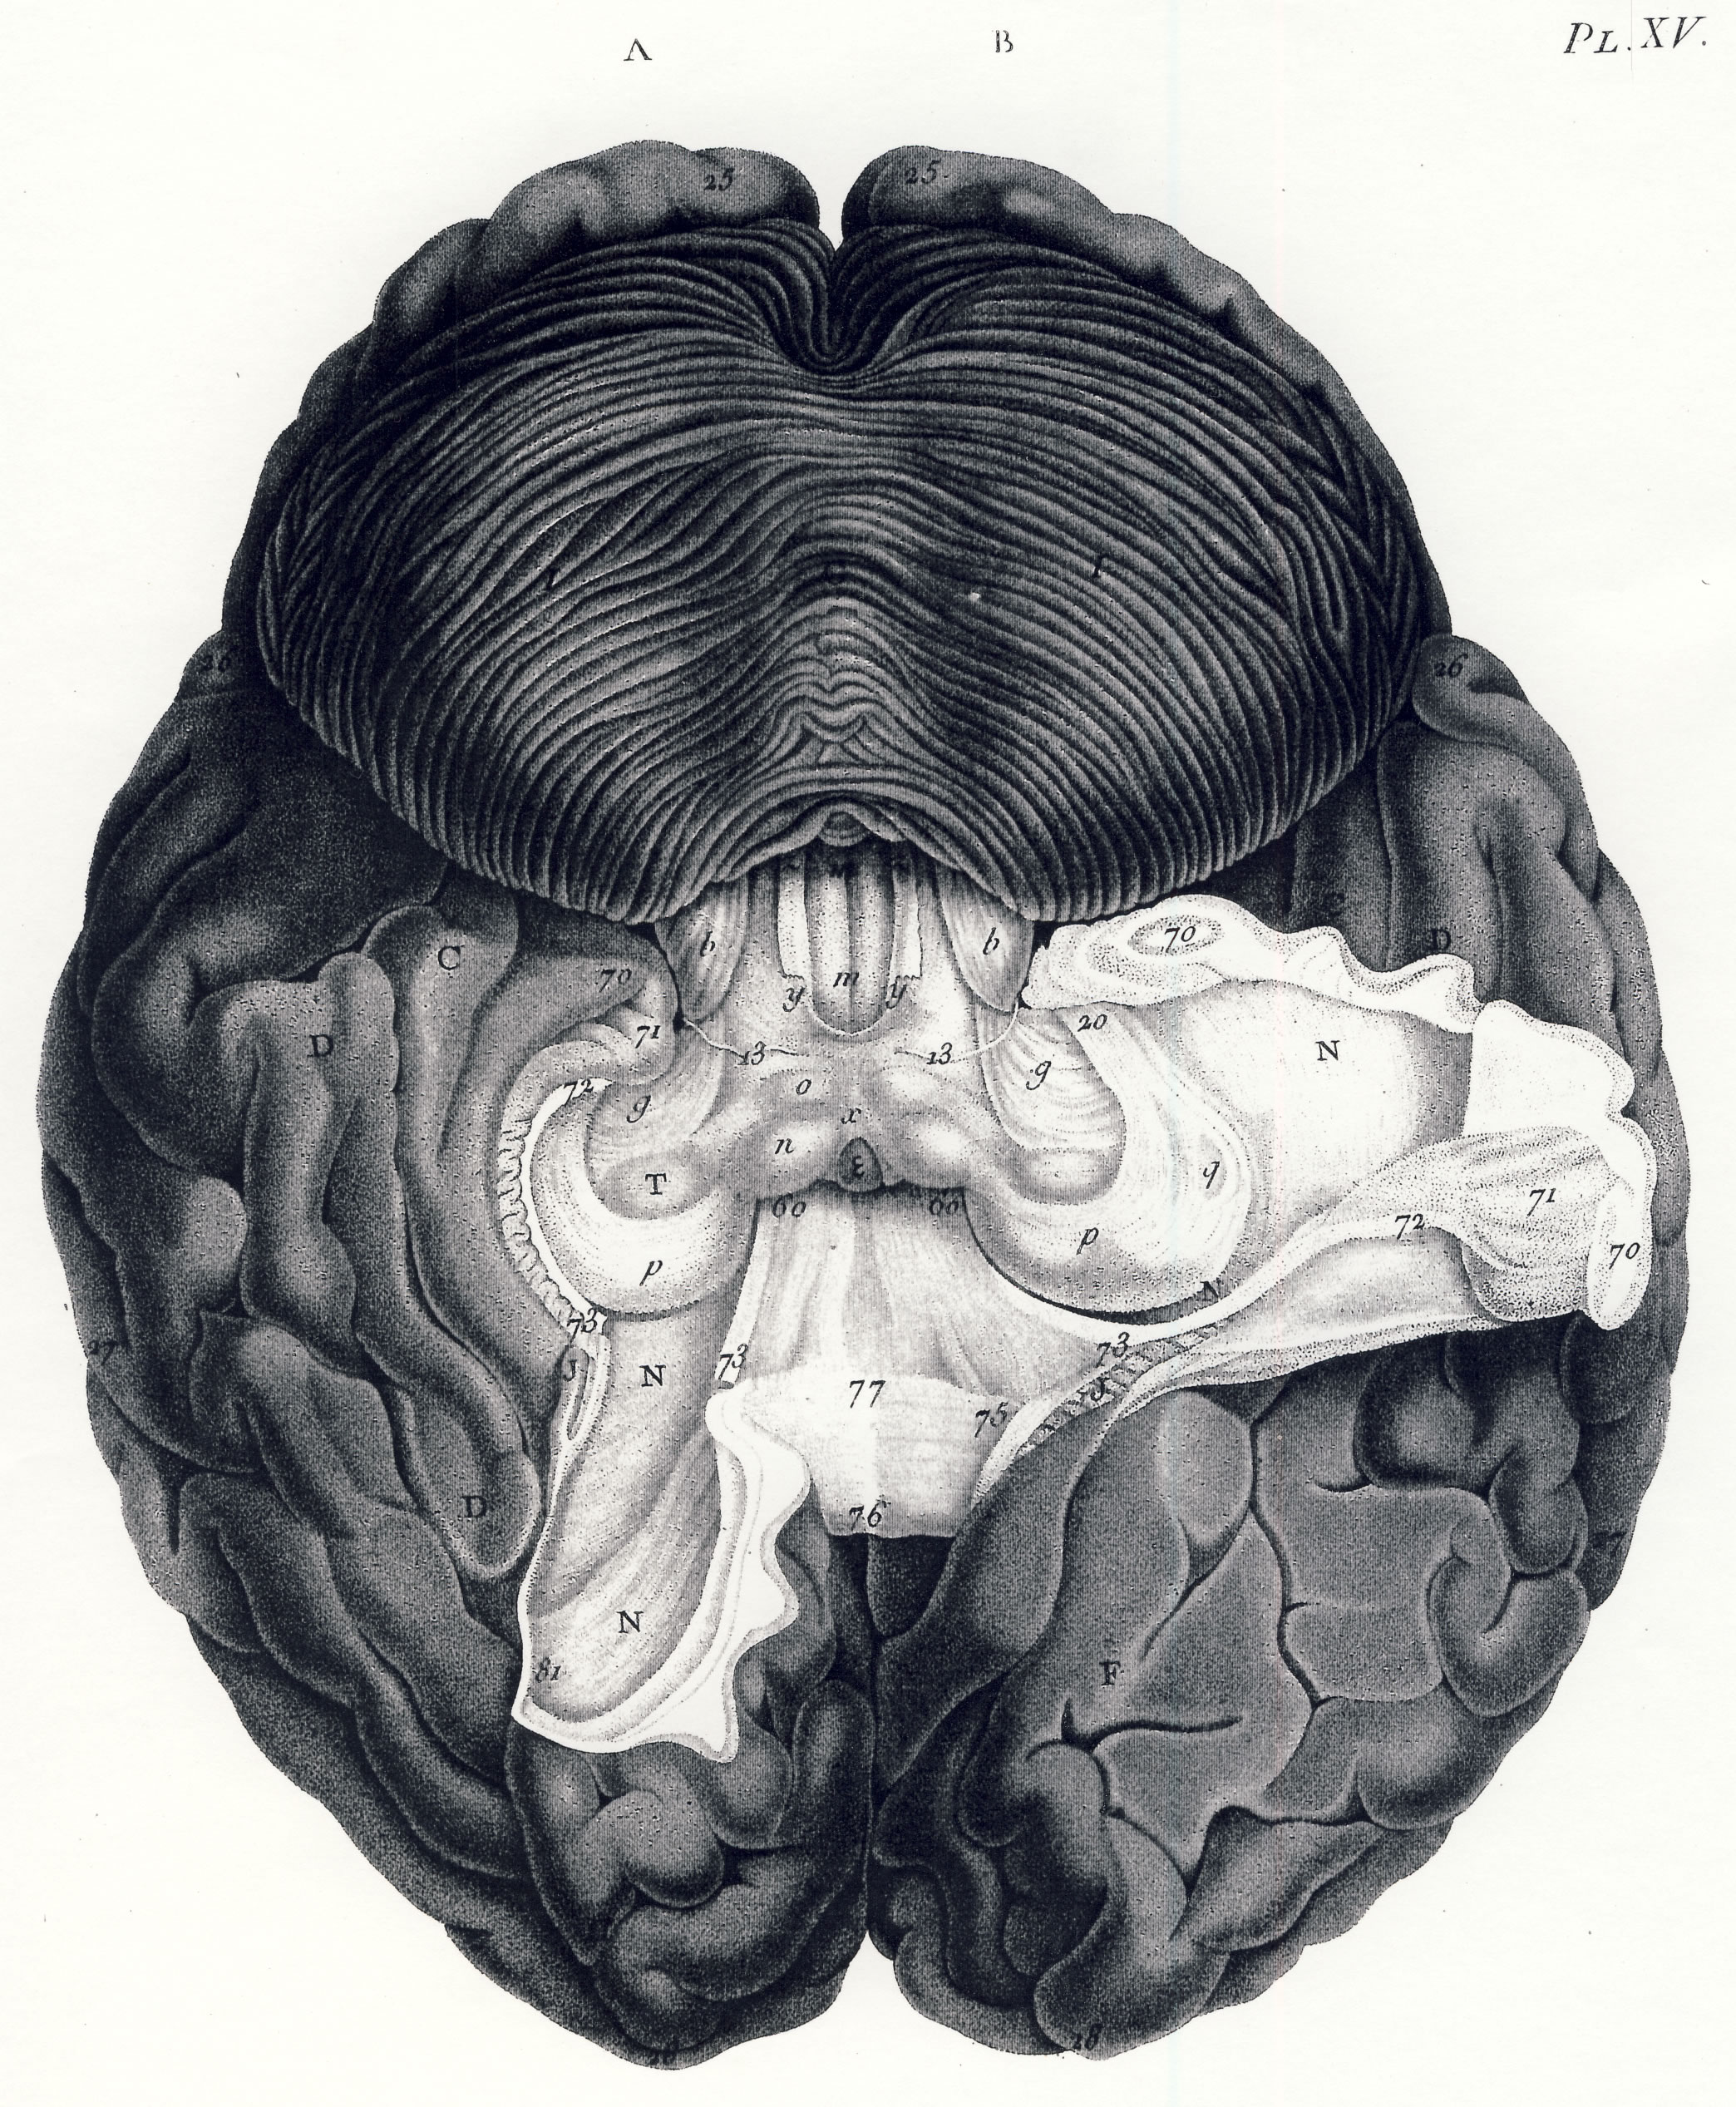

Gall, F. J. (1818). Anatomie et physiologie du système nerveux en général, et du cerveau en particulier, Avec des observations sur la possibilité de reconnoître plusieurs dispositions intellectuelles et morales de l´homme et des animaux, par la configuration de leurs têtes.

Librairie Grecque-Latine-Allemande, Vol. 3, I-XXXV u. 1-379 100 planches.